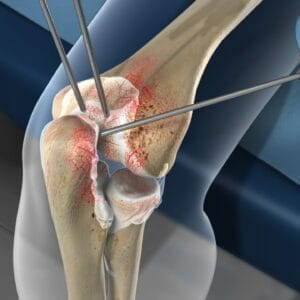

Elbow. Information for professionalsElbow Arthroscopy Overview What Is Arthroscopy? Arthroscopy is a minimally invasive surgical procedure that allows orthopaedic surgeons to diagnose and treat joint problems. The term “arthroscopy” is derived from the Greek words “arthro” (joint) and “skopein” (to look), meaning “to look within the joint.” During an elbow arthroscopy: A small